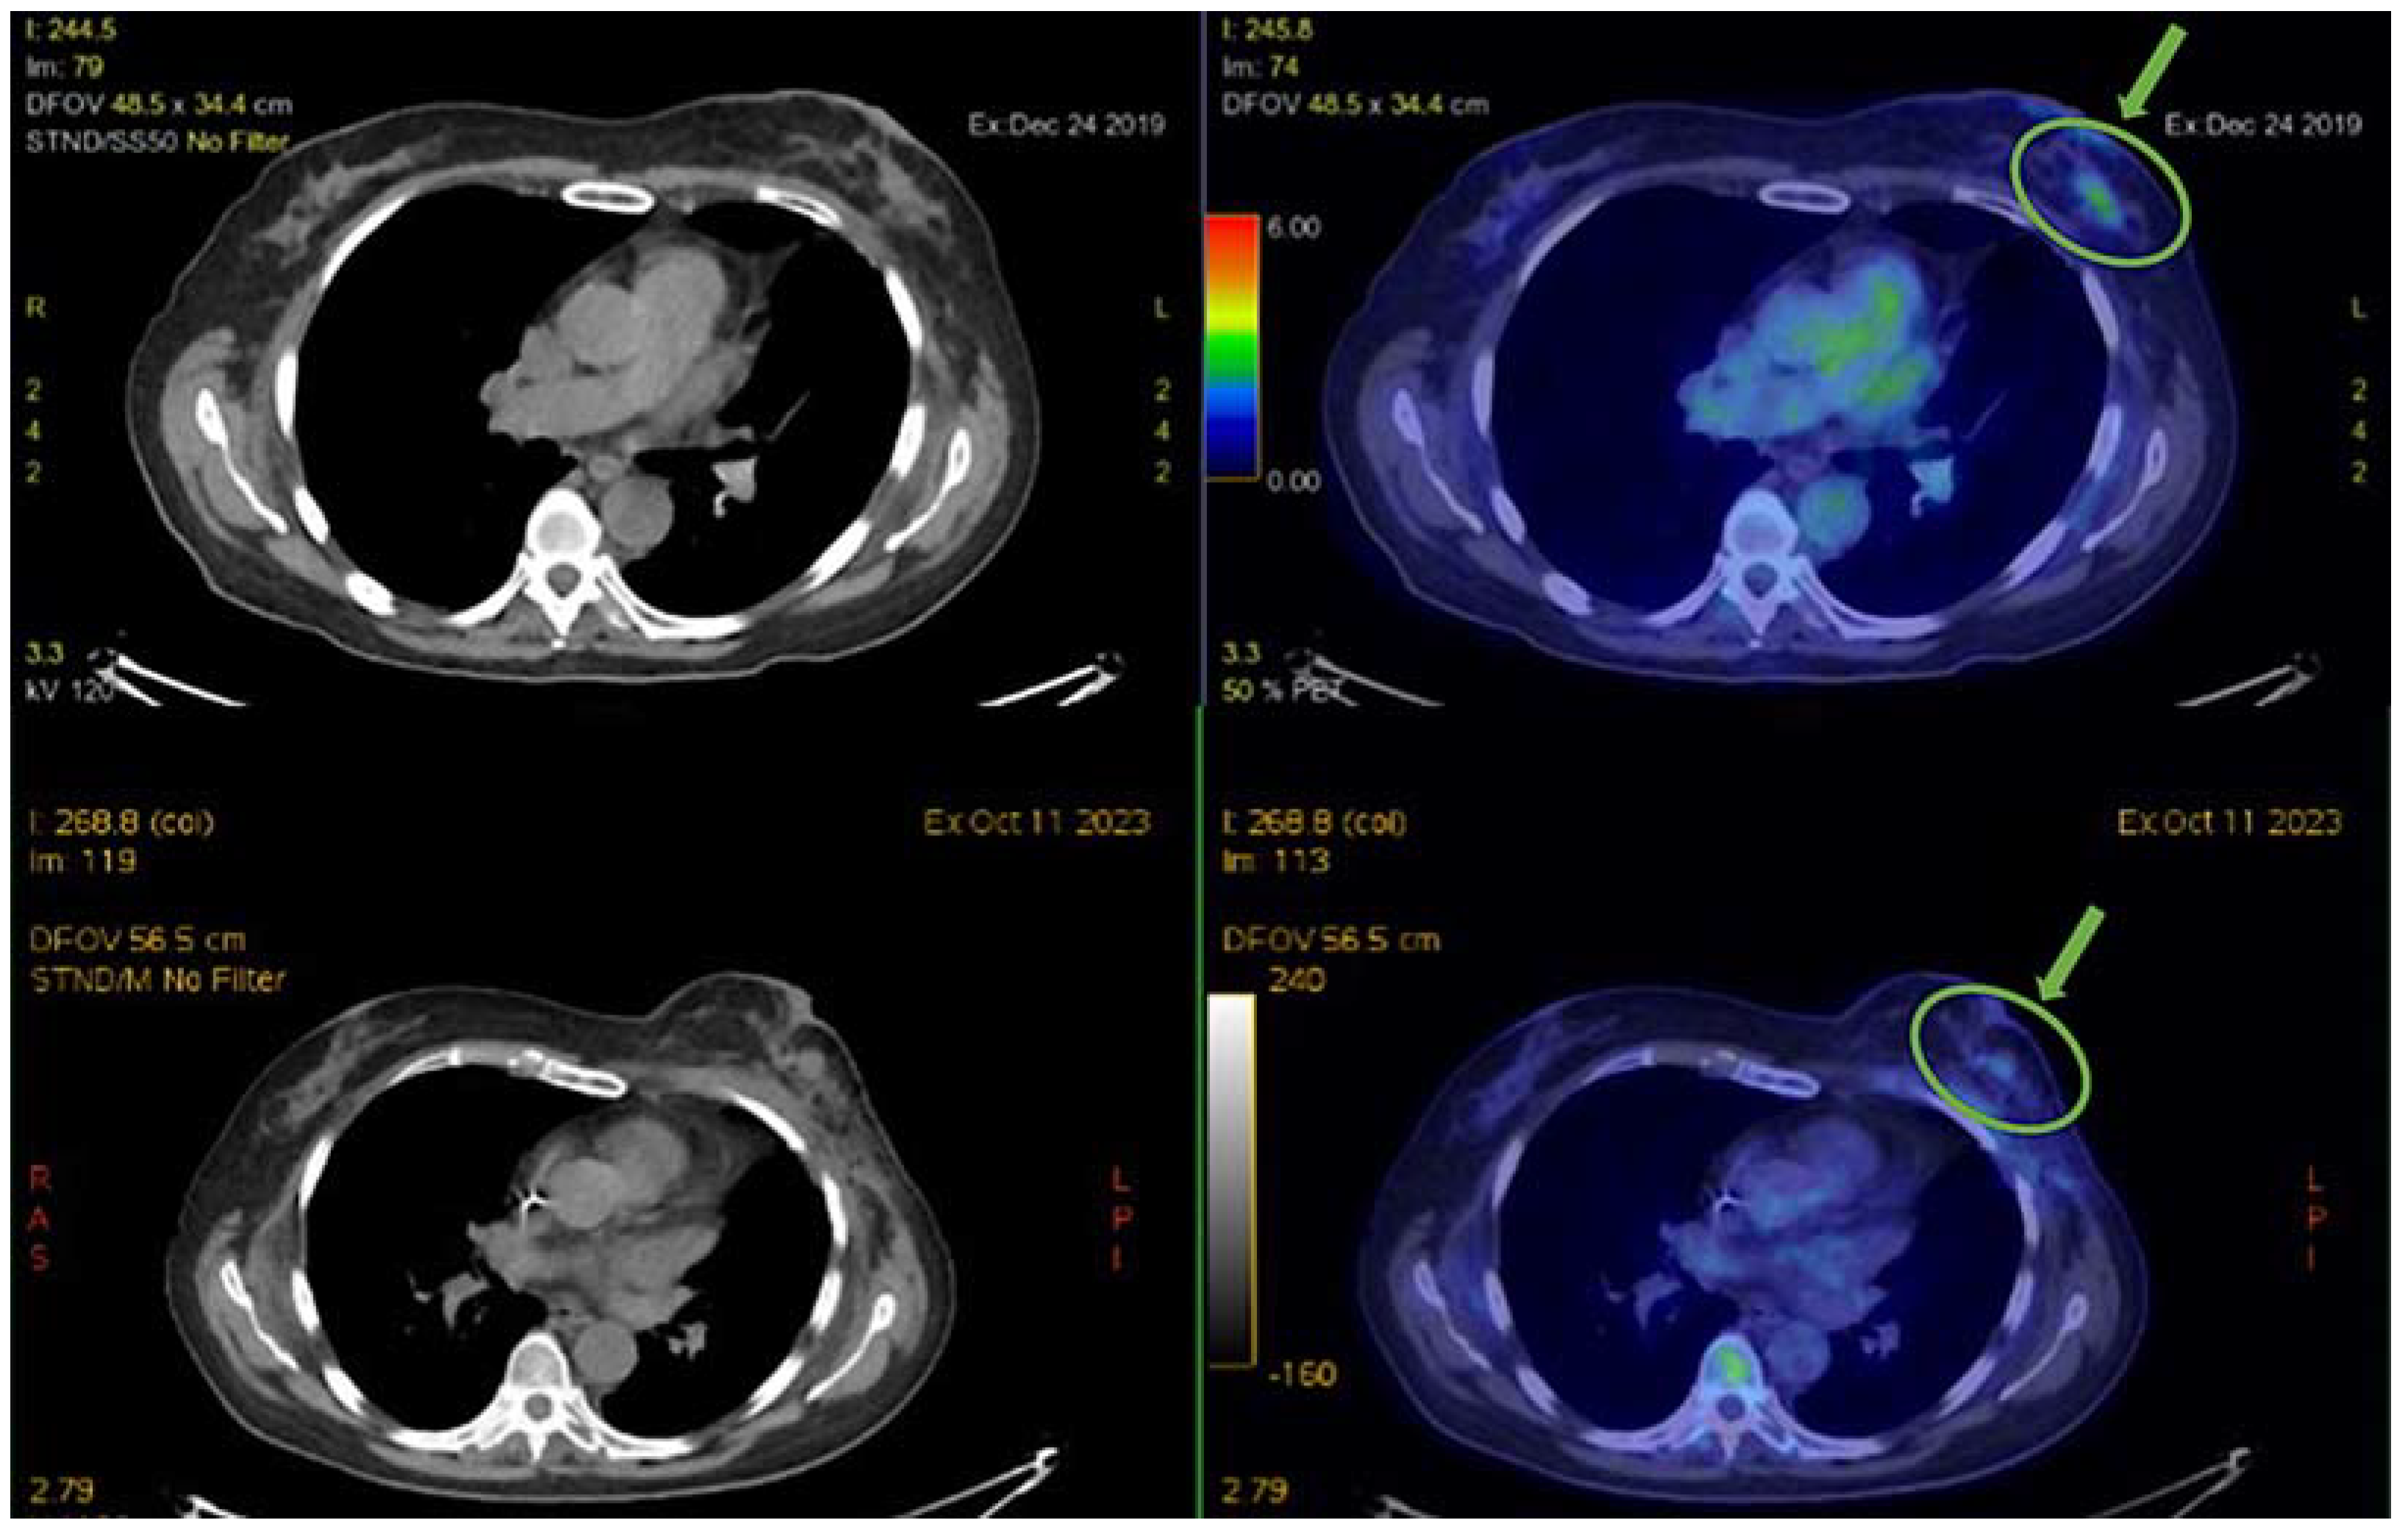

After 8 years, in 2019, a recurrence of skin nodules at the site of previous breast surgery was diagnosed. A biopsy showed a significant change in the biology of the disease, with the loss of hormone receptor expression (ER/PgR 0/0%), while HER2 remained negative, and the level of Ki-67 was 25%. The systemic staging of the disease with an 18-18F-fluorodeoxyglucose (FDG)—positron emission tomography (PET) scan showed a weak uptake at the level of the known skin nodules and bilateral axillary lymph nodes (the top of the image of Figure 2).

FDG-PET was performed to diagnose the patient’s breast cancer and then, during first-line mCHT and subsequent MTD chemotherapy, to follow the tumor’s response to therapy. A comparative analysis of the patient’s 2019 and 2023 PET images shows substantial stability/slight reduction of disease over a period of 4 years, from the diagnosis of metastatic disease to the present, highlighting the excellent control of the systemic disease obtained with the sequence of treatments carried out, as indicated by the green arrows and the ROI (region of interest) in Figure 2.

Figure 2. PET scan analysis before and after prolonged treatment. Top: 2019 PET scans; bottom: 2023 PET scans. The green arrow indicates the captured tracer and the ROI points to the region showing substantial disease control after 4 years.